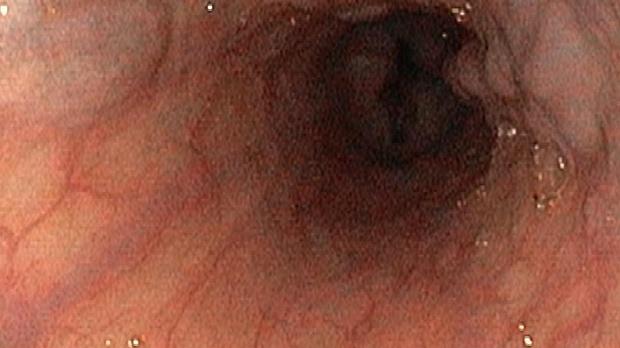

Появление ультратонких гастроскопов с высоким разрешением и технологией NBI (оптического узкоспектрального режима) компания OLYMPUS сделала возможной гастроскопию экспертного уровня под местной анестезией, без наркозных рисков.

Ультратонкие гастроскопы GIF-XP170N и GIF-XP190N с параметром оптики Close Focus, который позволяет приближаться к слизистой на минимальную глубину резкости до 2 мм, обеспечивают качество изображения, сопоставимое с аппаратами экспертного класса.

В Центре Экспертной Эндоскопии, г. Симферополь с июня 2018 с помощью этих эндоскопов выполнено более 1000 эндоскопических исследований, с полным соблюдением критериев качества ESGE. Среднее время исследования составило 14мин. 51с. Все исследования выполнялись с предварительной подготовкой желудка, применением водяной помпы и СО2-инсуффлятора, фото- и видеодокументацией.

Использование в ежедневной рутинной практике современных ультратонких эндоскопов высокого разрешения с технологией оптического узкоспектрального режима (NBI® OLYMPUS™) под местной анестезией позволило полностью обеспечить соответствие критериям качества выполнения эндоскопических исследований, определенным ESGE. Данный метод комфортен для пациента под местной анестезией, безопасен, является простой и удобной альтернативой ЭГДС под седацией, что особенно важно в амбулаторных условиях.